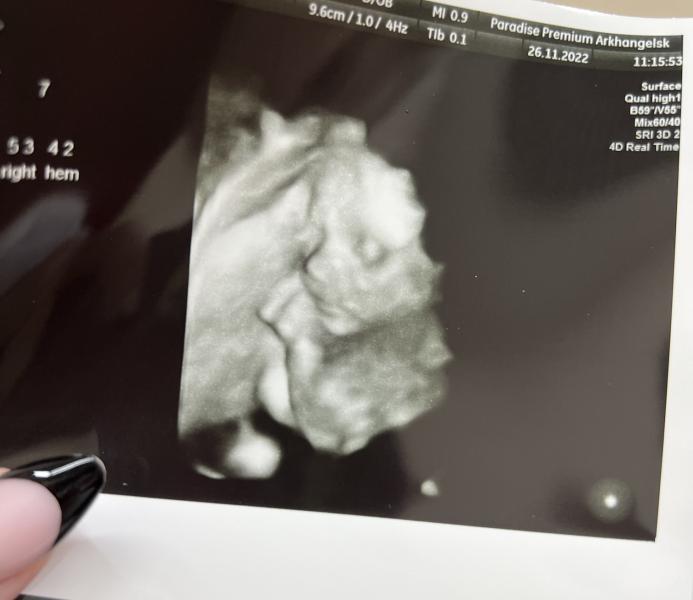

2 скрининг: сыночек бушевал, но все хорошо!

Сходили на 2 скрининг 🙏

Сыночек бушевал , датчик пинал 😀

Слава богу все хорошо , вес 400 грамм , растём дальше 💙